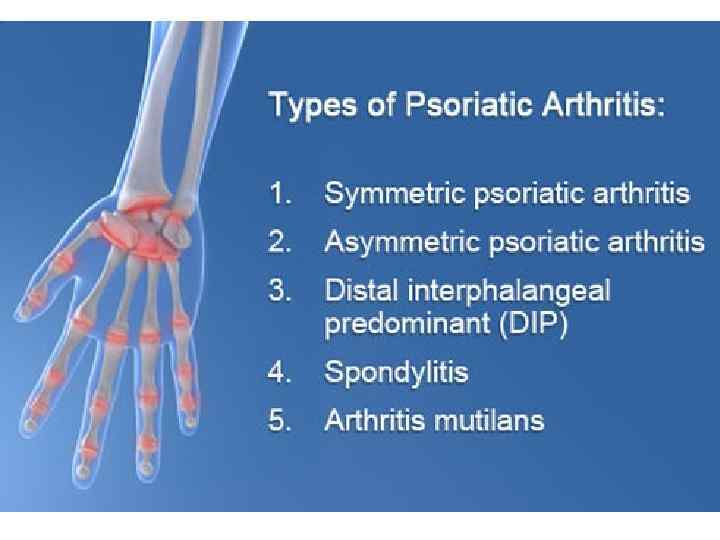

Psoriatic arthropathy

Psoriatic arthropathy